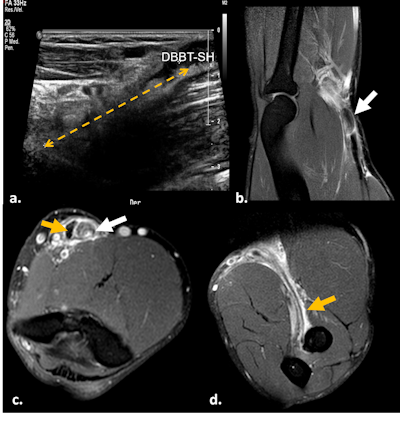

Quadriceps tendon rupture. Fat-suppressed proton density-weighted coronal (a) and axial (b) images show complete rupture of the conjoined portion of the vastus medialis and lateralis tendons of the quadriceps at its medial margin, with torn end retracted 2 cm (red arrow). Lateral insertion into the patella is preserved (white arrows). Complete rupture of the intermediate vastus (yellow arrow).